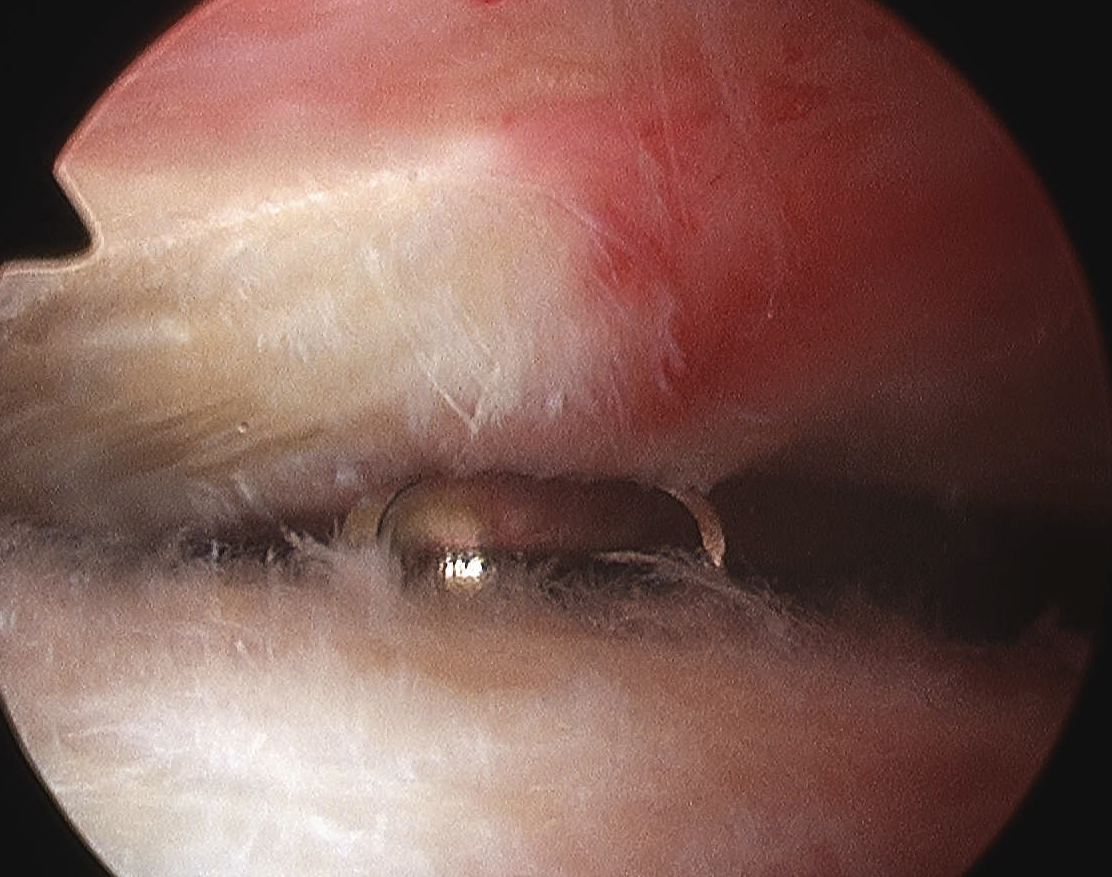

Arthroscopic acromioplasty

Technique

Beach chair / lateral

- posterior viewing portal subacromial space

- lateral working portal

- bursectomy with shaver

- electrocautery to release / resect CA ligament

- use burr to perform anterior acromioplasty

CA ligament above shaver and cuff

Large acromial spurs

Spur resection